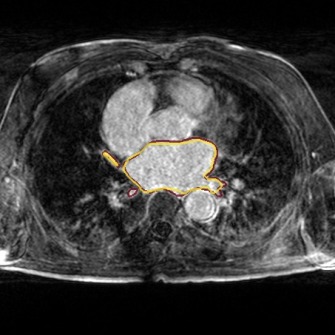

Results. We compared our approach against three other reconstruction methods: RecNet111https://github.com/js3611/Deep-MRI-Reconstruction [14] (i.e. the proposed approach without refinement step), DAGAN222https://github.com/nebulaV/DAGAN [16] using both adversarial and perceptual loss, and DLMRI333http://www.ifp.illinois.edu/~yoram/DLMRI-Lab/DLMRI.html [10], a dictionary learning based method. No data augmentation was used for any of the methods.

We show the results of our evaluation in Table 1, and a sample reconstruction in Figure 2. RecNet performed best in terms of PSNR, which is expected as its training objective directly corresponds to this metric, but its reconstructions were over-smoothed. DLMRI had the lowest MOS, with its reconstructions showing heavy oil paint artifacts. DAGAN, combining MSE loss with a visual loss function without any further precautions, suffered from low PSNR. While its reconstructions also looked sharp, they were noisy and often displayed aliasing artifacts, which was reflected in a lower MOS compared to our method. Our proposed approach achieved significantly444Significance determined by a two-sided paired Wilcoxon signed-rank test at . higher mean opinion score than all other methods, while still maintaining high PSNR. Reconstructions obtained by our method appeared sharper with better contrast. Moreover, our method achieved the highest SIS close to segmentation performance on the ground truth data, which indicated that the segmented objects were clearly visible in the reconstructed images.

These results further demonstrate that PSNR alone is a subpar indicator for reconstruction quality, making our SIS a useful supplement to those metrics. For our method, SIS agreed with the quality score given by the expert user. Somewhat surprising is that the SIS of DLMRI is slightly higher than RecNet and DAGAN although DLMRI has the worst MOS. We conjecture this is because, although DLMRI reconstructed images lack textural details, areas belonging to the same organ have similar intensity values, which helps the segmentation task. While scoring through an expert user is thus still the safest way to evaluate reconstructions, we believe that in conjunction with PSNR, SIS is a helpful tool to quickly judge image quality during the development of new models.

The following images show more samples for 8-fold undersampling. For each of the seven patients of the test set, a random slice showing the left atrium was selected. The contour of the predicted segmentation of left atrium is shown in yellow, the contour of the ground truth segmentation in red.